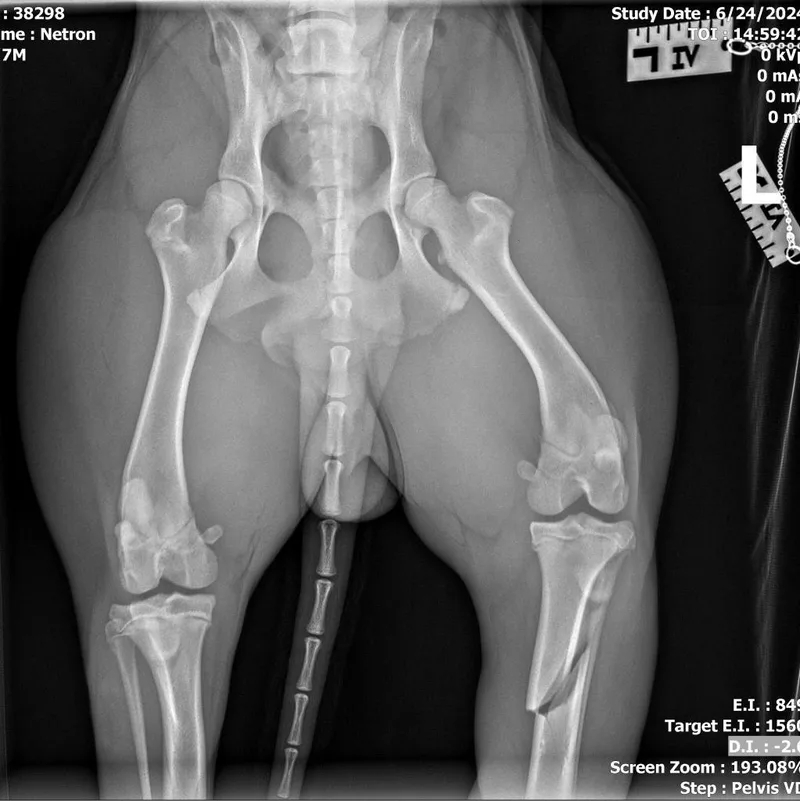

appears to have a displaced tibia fracture; this fx may be able to be set and splinted but will need to be set in alignment; x-rays have been reviewed by an off-site vet